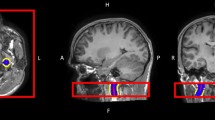

Perfusion parametric maps calculated from AIF_A and from AIF_SA for a randomly selected participant are shown in Fig. 7. Both Ktrans and ve were obviously lower in the lumbar vertebra when the perfusion parameters are calculated using AIF_A compared to AIF_SA.

Maps of the perfusion parameters including Ktrans, Kep, ve, and vp for one participant, using an aortic arterial input function (AIF; top row) or a segmental arterial AIF (bottom row).